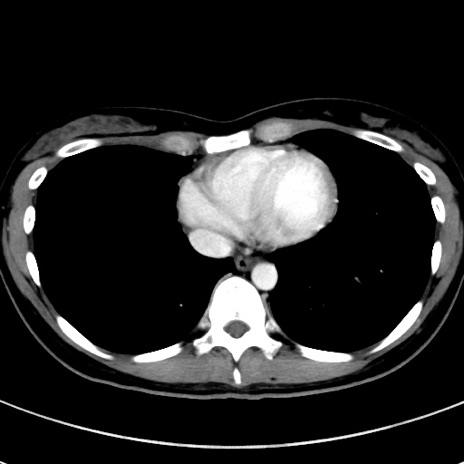

症例17(横断像)

【症例】20歳代女性

【主訴】嘔吐、下腹部痛

【現病歴】昨日夕食後に嘔吐し下腹部痛が出現。本日になっても嘔吐持続し改善しないため来院。

【身体所見】意識清明、BT 37.2℃、BP 108/67mmHg、腹部:平坦、やや硬、下腹部正中から右にかけて圧痛あり、反跳痛軽度あり、tapping pain(+)。

【データ】WBC 13600、CRP 14.94